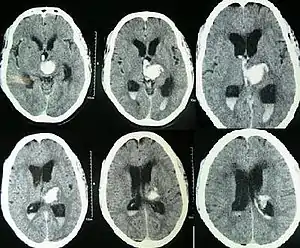

| CT scan showing spontaneous intracerebral hemorrhage with bleeding in the third and both lateral ventricles and hydrocephalus[1] | |

30% of intraventricular hemorrhage (IVH) are primary, confined to the ventricular system and typically caused by intraventricular trauma, aneurysm, vascular malformations, or tumors, particularly of the choroid plexus.[2] However 70% of IVH are secondary in nature, resulting from an expansion of an existing intraparenchymal or subarachnoid hemorrhage.[2] Intraventricular hemorrhage has been found to occur in 35% of moderate to severe traumatic brain injuries.[3] Thus the hemorrhage usually does not occur without extensive associated damage, and so the outcome is rarely good.[4][5]

Diagnosis can be confirmed by the presence of blood inside the ventricles on CT.[7]

Prognosis is very poor when IVH results from intracerebral hemorrhage related to high blood pressure and is even worse when hydrocephalus follows.[1] It can result in dangerous increases in ICP and can cause potentially fatal brain herniation.[1] Even independently, IVH can cause morbidity and mortality. First, intraventricular blood can lead to a clot in the CSF conduits blocking its flow and leading to obstructive hydrocephalus which may quickly result in increased intracranial pressure and death.[13] Second, the breakdown products from the blood clot may generate an inflammatory response that damages the arachnoid granulations, inhibiting the regular reabsorption of CSF and resulting in permanent communicating hydrocephalus.[2][13]